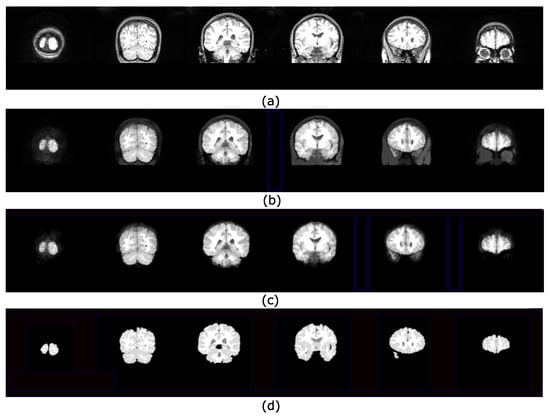

4.2. Brain Extraction Based on Hyperconnected Functions and Lower Leveling